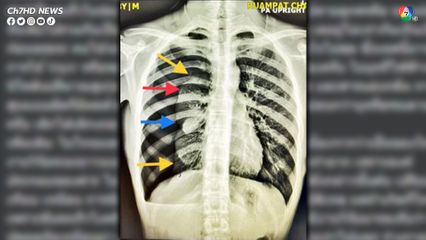

โดยคุณหมอ ได้โพสต์ระบุข้อความบรรยายว่า "วันนี้มีเรื่องมาเล่าอีกแล้ว อาจารย์ เด็ก16 เจ็บหน้าอก เสียงคุณพยาบาลเสียงใส เดินมาแจ้ง OMG เป็นไปได้ไง ... ซักประวัติ น้องรูปร่างผอม สูบบุหรี่ไฟฟ้าจัด บอกว่าเจ็บหน้าอกเวลาหายใจ ไม่ได้ยกของหนัก เอ็กซเรย์ดังรูป

สรุปเป็นลมรั่วในช่องปอดขวาทำให้ปอดขวาแฟบครับ ปลายลูกศรคือ ขอบปอดที่แฟบไปรวมกันเป็นก้อนตรงกลาง โดยปอดขวามี 3 พู เลยยู่ไม่เท่ากันเห็นเป็นก้อนขรุขระ คนไข้จะมาด้วยเหนื่อยหรือเจ็บหน้าอกหายใจไม่สุด